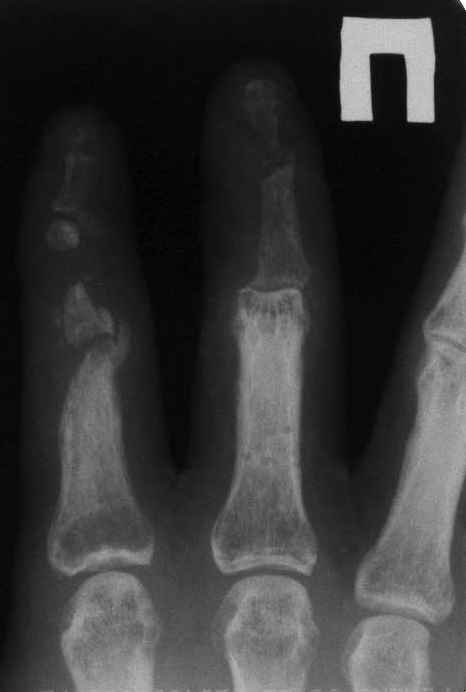

33 yo male motocross rider crashed after a jump sustaining isolated bilateral femur fxs, R side with a basicervical femoral neck and ipsilateral mid-distal 1/3 shaft, L side with a subtroch/prox 1/3 femur fx. Pt was HD stable, no LOC, GCS - 15, No other injuries, spines cleared.

basicervical neck is normally treated with hip screw or cephalomedullary nail.

after perfect reduction (either closed or open) i would attempt 1 implant to treat both (i.e. TFN or Intertan). can do anything though like Dr. Routt mentioned. intertan is nice because of the rotational stability it imparts in the neck

i would use an antegrade nail on the left

Chip Routt listed all main options. The right proximal fracture looks closer to trochanteric. Most elegant solution would be to fix all with a single implant with minimal incisions. Long Gamma nail or any other reconstruction or proximal type nails are suitable. Technically less demanding wiuld be temporary neck pinning as is, retrograde nailing of the shaft, then final reduction and fixation of the trochanteric fracture as isolated, by DHS with 2 holes plate. Good luck.